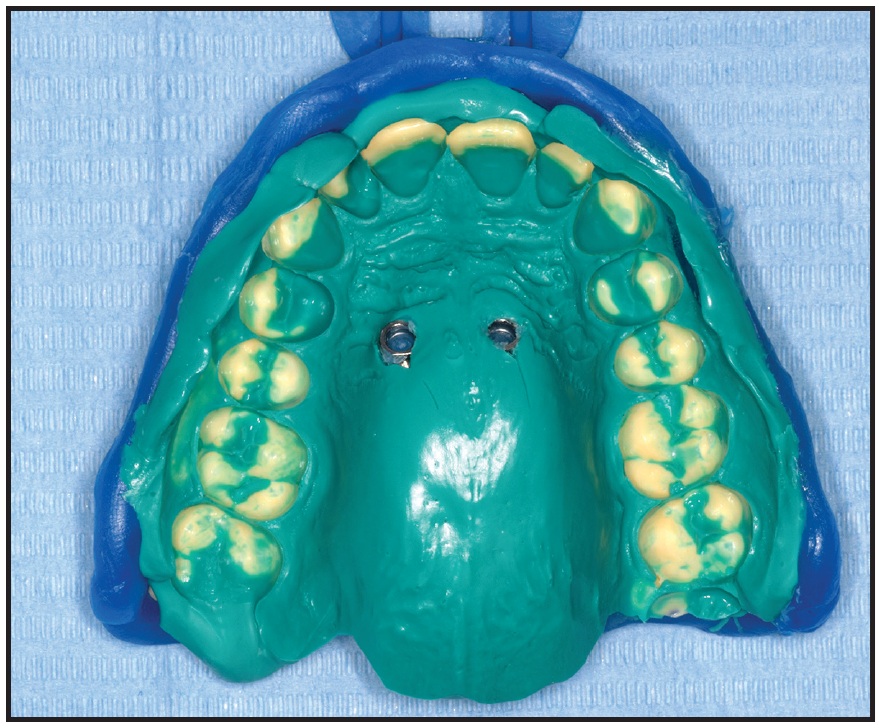

After impression transfer copings were placed over the miniscrew heads, a precision impression was taken with vinyl polysiloxane, and the miniscrew positions were replicated with two analogs (Fig. 10). A hybrid Hyrax‡‡ expander was fabricated with an anterior arm on the right side and an attached eyelet that would serve as an occlusal guide for traction of the impacted canine (Fig. 11). The arm was designed to generate a force vector capable of moving the canine crown distally and occlusally, thus facilitating guided eruption.

Fig. 10 Vinyl polysiloxane impression with two miniscrew analogs.